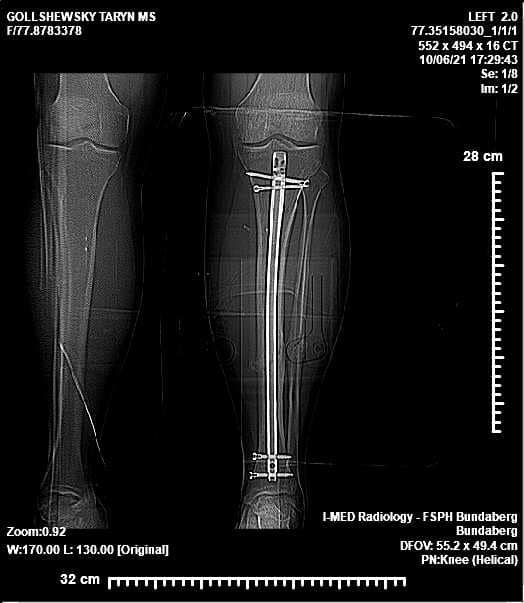

Only 10 months ago, discus thrower Taryn Gollshewsky's Olympic dream was shattered when she broke her leg playing soccer in the lead up to Tokyo.

The Bundaberg local had to learn to walk again — but now, after only 10 weeks of training, she has taken out gold at the 2022 Australian Athletics Championships, held in Sydney at the weekend.

The 29-year-old was sensationally sidelined from Olympic preparations when she broke her leg during a soccer match in the Wide Bay.

"I was bed ridden for two-and-a-half weeks and then I was on crutches for about eight weeks," she said.

"With discus I am rotating, and I am twisting – so with the torque and the rotational forces that go through my leg, I was at risk of re-breaking my leg," Ms Gollshewsky said.

"I still have some physical limitations and there is still a little bit of pain associated with that injury, but we're on the way up which is really positive."